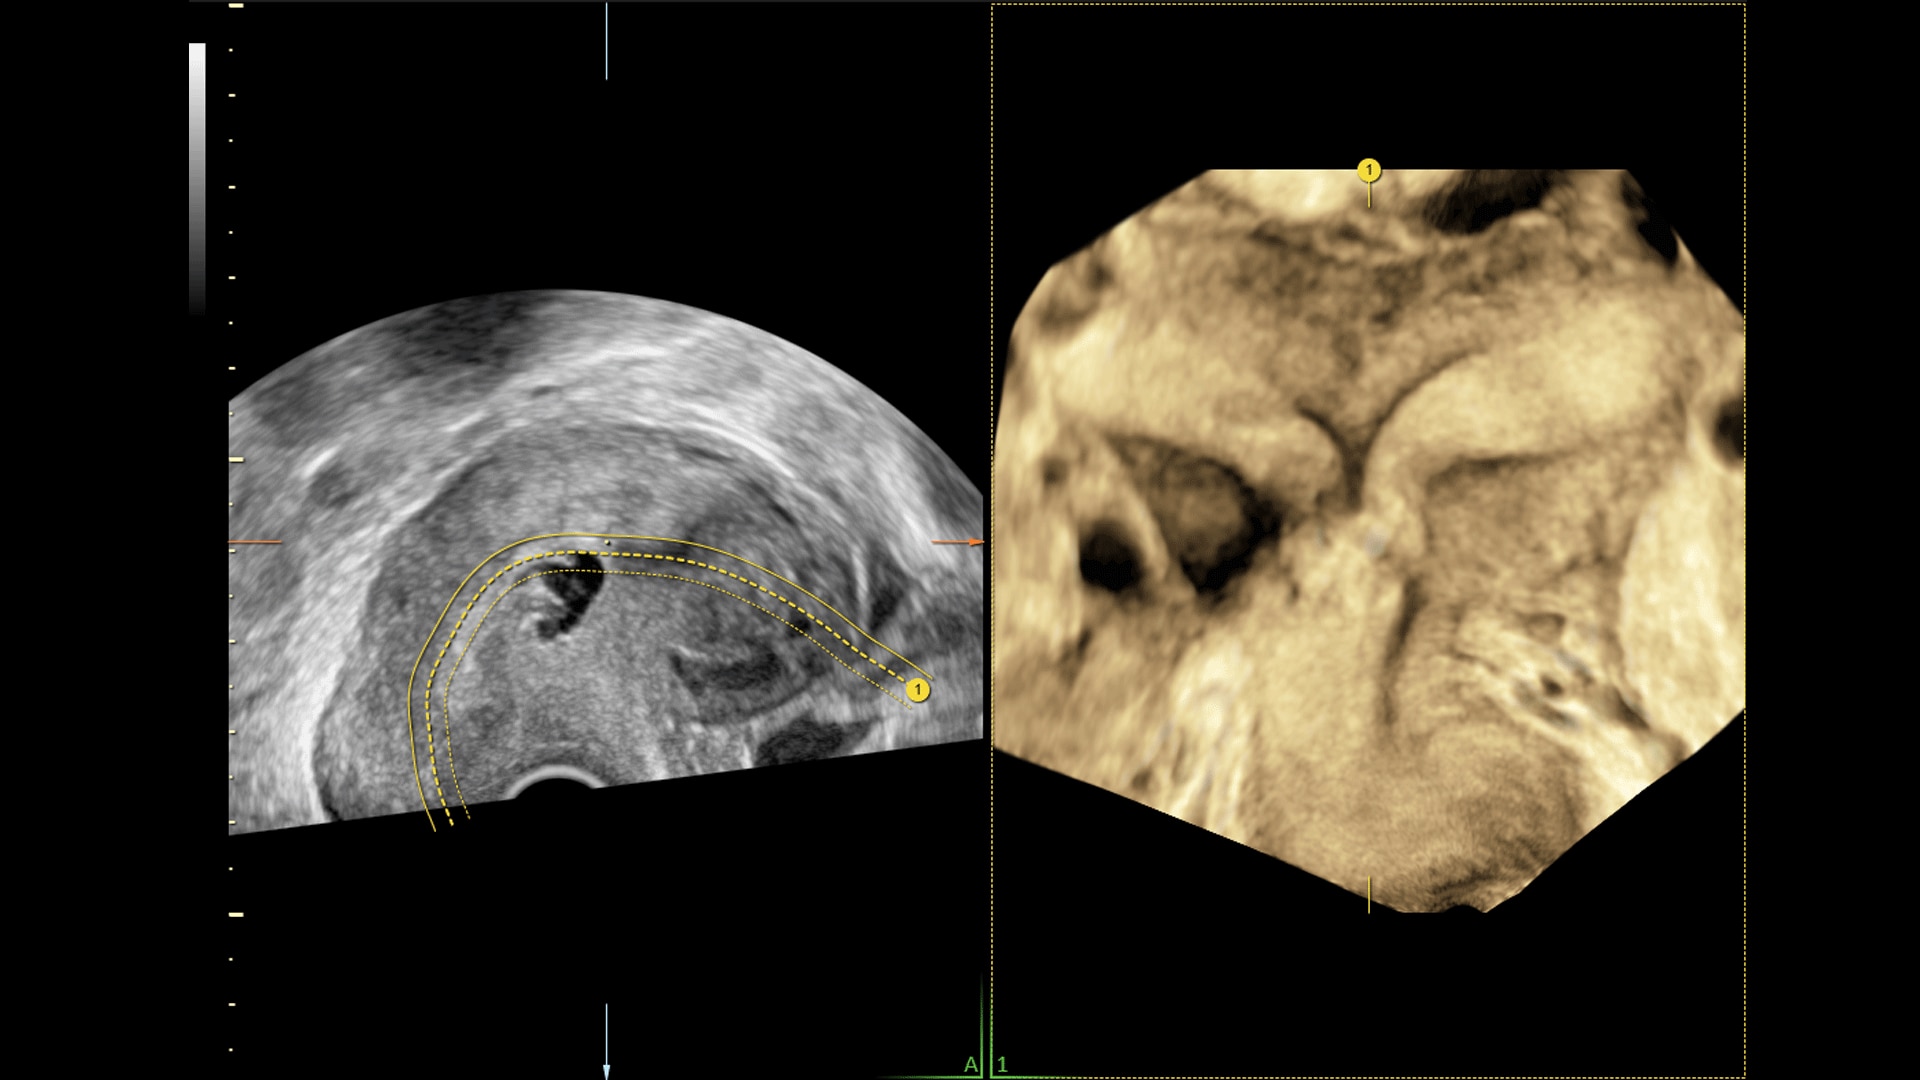

Amplify imaging performance and simplify scanning with our most advanced architecture

Extraordinary clarity and definition so you can focus on early detection and intervention.